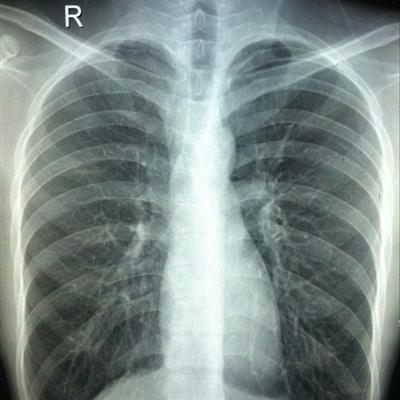

Osteosarcoma lung cancer which is more serious?

First, although great progress has been made in the treatment of lung cancer, such as the comprehensive treatment of surgery, radiotherapy and chemotherapy, and the advent of new anticancer drugs, the prognosis of lung cancer is still very poor. The 5-year survival rate of lung cancer patients receiving treatment is 14%, while it was 11% 30 years ago. The high mortality rate of lung cancer is mainly due to the lack of early diagnosis and effective treatment, even for early patients Most of them were systemic diseases at the time of initial diagnosis.

Third: the mid-term lung cancer can be surgically removed, but according to the strict staging of lung cancer, the evidence is judged by the thoracic surgeon. Advanced lung cancer is difficult to cure, only through a variety of methods of comprehensive treatment. For example, using percutaneous argon helium cryoablation of primary lesions and metastatic lesions, to achieve similar local surgical resection effect. Combined with chemotherapy or targeted therapy to achieve the best therapeutic effect, reduce symptoms and prolong life.